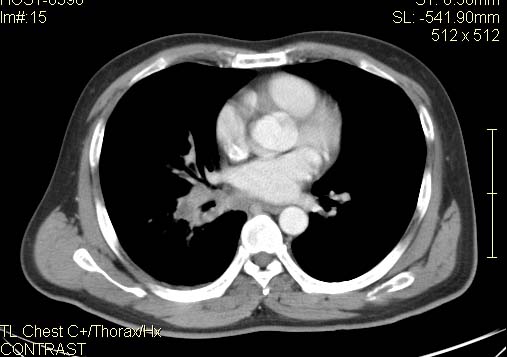

以下是引用qc80012345在2007-4-17 12:33:00的发言:[br]右肺下叶周围型肺癌伴肺门及纵隔内淋巴结转移;比较清楚。

以下是引用qingyuan在2007-4-17 14:19:00的发言:[br]右肺下叶外侧后段胸膜下区节结样病变、分叶、内可见空洞,壁厚薄不均,胸膜凹陷、肺门周围区纹理增粗、僵硬、并近似小结节样改变,肺门区软组织节结、纵膈淋巴结肿大,患者病史长、抗炎治疗无好转炎性改变基本排除,考虑:右肺下叶周围型肺癌伴纵膈及右肺门区淋巴结转移、肺内淋巴管受侵。